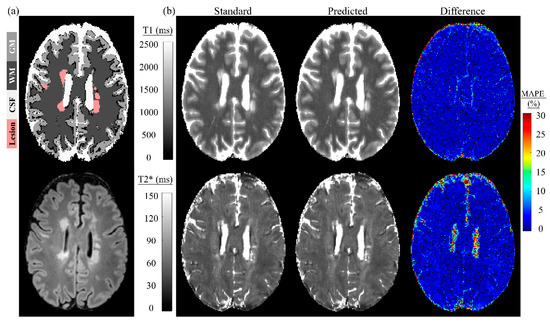

Figure 6 displays a Bland–Altman plot for all subjects of dictionary matching and the two-stage model. The fifth and sixth columns of Table 2 and Table 3 lists the mean and difference (with standard deviations) between them. A significant positive correlation was observed for the whole brain for T1 and T2* in the validation dataset and T2* in the testing dataset. The significant positive correlation also appeared in the CSF for T2* for both validation and testing datasets. A significant negative correlation was observed for the MS lesion for T2* in the testing dataset. In both validation and testing datasets, the mean difference was less than or equal to 10 ms for GM and WM, and 5 ms for the MS lesion, for T1. The mean difference was less than or equal to 0.7 ms for GM, WM, and the MS lesion for T2* in both validation and testing datasets. Figure 7 depicts a single slice from an MS patient for the tissue masks, FLAIR, standard and predicted maps for T1 and T2*, and their corresponding difference maps. The standard maps were obtained by dictionary matching using the inner-product method, and the predicted maps were gathered by the proposed two-stage model. The MAPE for GM, WM, and MS lesions was low. The MAPE was higher for the CSF region compared with other tissue types in the difference map, especially for T2*.

Figure 7.

Magnetic resonance fingerprinting parametric maps of a single slice in an MS patient matched by the simulated dictionary (standard) and predicted by the proposed model. (a) Top is the tissue masks; bottom is the FLAIR. (b) Standard maps by dictionary matching, predicted maps by the proposed two-stage model, and difference maps between them.